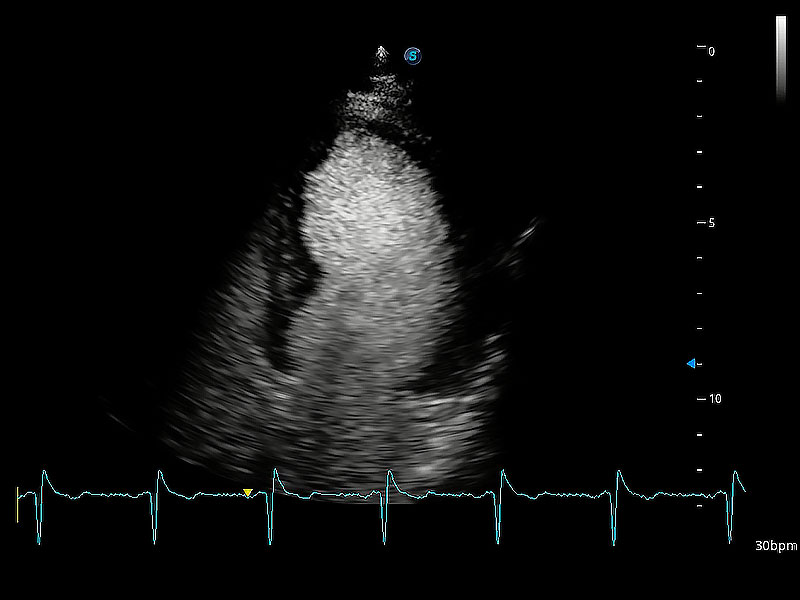

ProPet 80 配备了丰富的心脏探头群、先进的成像技术和专业的心脏测量工具,可帮助动物医生为不同体型和生理结构的动物提供心脏和心肌功能的全面评估。

通过360度任意调节3条M型取样线,在同一心动周期上观察心脏不同位置的运动曲线,得到准确的心功能测量数据,有效评估心肌运动及左心室功能。